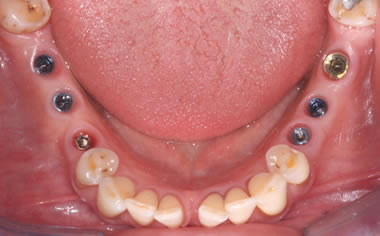

Full arches of teeth replaced by dental implants

Case One (5 images)

Full set of lower teeth fixed onto five dental implants.